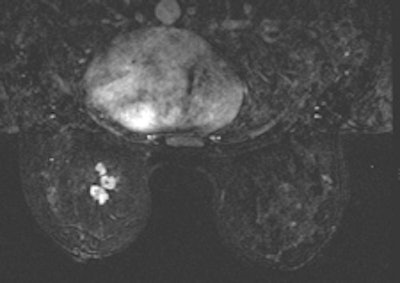

Targeted ultrasound for the palpable lump in the left breast showed vague hypoechoic area at 12 o’clock which was core biopsied under ultrasound guidance (left). Pathology of left breast ultrasound core biopsy was benign, however at multidisciplinary breast care conference, pathology result was found to be discordant with imaging findings on ultrasound, and further evaluation with breast MRI (right) showed an irregular enhancing left breast mass in the upper, central to inner breast which was confirmed to be invasive ductal carcinoma on excisional biopsy."Diagnosis doesn't stop with the biopsy; it's even more important to correlate the biopsy results with the imaging finding," she said.